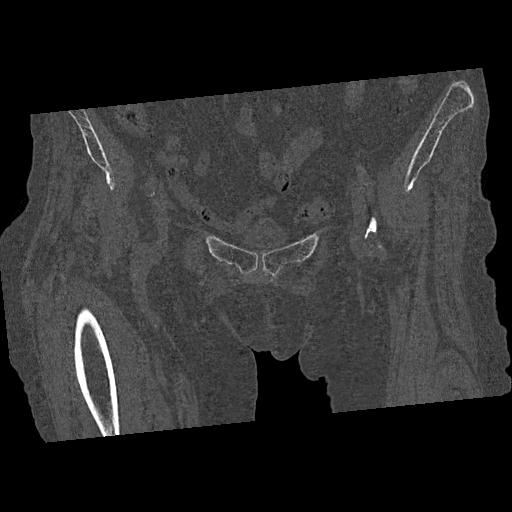

110286 2/17 股関節 2R 74歳女性 右人工骨頭

82084 1/14 1/20 股関節 2R 78歳男性 右人工骨頭

102811 1/13 股関節 2R 1/19 2R 80歳女性 右DHS